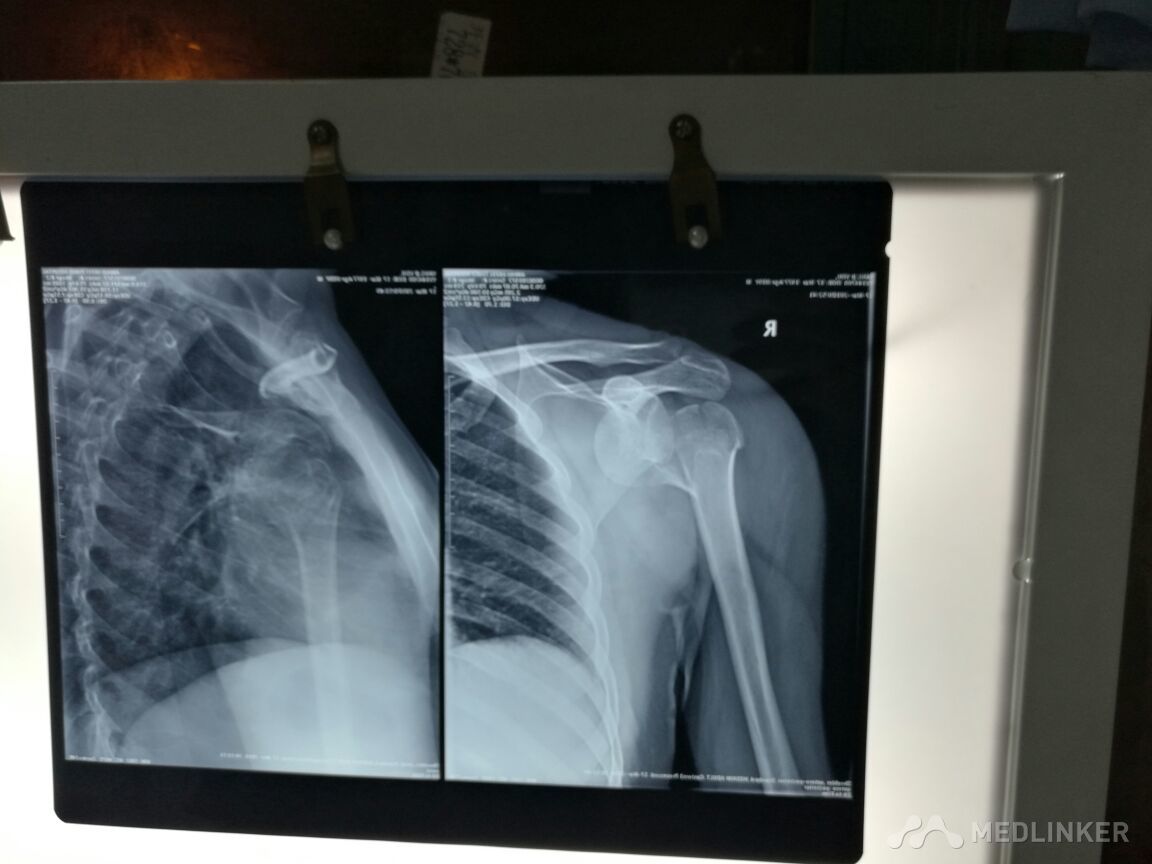

请教各位老师,这个病人手术方式,患者,男,39岁?

合肥瑞康骨科医院

发布于 16-03-17 21:56